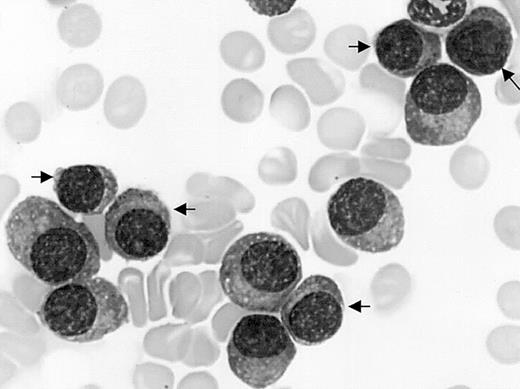

Mature plasma cell morphology. Bone marrow myeloma cell infiltrate by mature malignant plasma cells including 45% of small mature plasma cells (arrows) in a patient with CD20+ MM and t(11,14). May-Grünwald-Giemsa staining; original magnification, × 1000.

Twelve (18%) of 66 patients had more than one third of their tumor cells expressing CD20 and 5 patients (7%) expressed CD20 on 100% of their tumor cells. These 5 patients were observed only at diagnosis and represent 5 (10%) of 50 patients. CD20+ MM expressed neither CD19 nor CD22. We have looked for correlations between CD20 and morphology. Seven (58%) of 12 patients with CD20+ MM had a small mature plasma cell morphology (ie, > 30% small plasma cells) versus 4 (7%) of 54 patients with CD20- MM (Fisher exact test, P = .0001; Figure 1). Four of 5 patients with 100% CD20+ MM had a small plasma cell type morphology In addition, none of the CD20+ MM cases showed any plasmablastic cells nor any significant amount of immature myeloma cells (ie, < 6% of cells). The 14q32 chromosomal abnormalities were normally distributed (data not shown) in the 66 patients. A strong correlation was found between CD20 and t(11;14). Indeed, 10 (83%) of 12 patients with CD20+ MM had a t(11;14) versus 5 (9%) of 54 CD20- MM patients (P < .0001). Of note, 5 of 5 MM patients with 100% CD20+ MM cells had a t(11;14). Conversely, 10 (66%) of 15 MM patients with a t(11;14) had CD20+ MM versus 2 (4%) of 51 MM patients lacking t(11;14) (P < .0001). In addition, all 6 cases with t(4;14) and cases with other 14q32+ rearrangements were restricted to the patient population with CD20- MM.